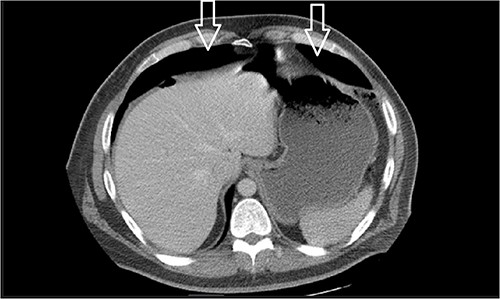

Dietary consultation started him on a gastroparesis diet where he progressed well. Upon hospital discharge CT showed a moderate volume of pneumoperitoneum with a small volume of perihepatic and perisplenic ascites. No areas of focal bowel wall thickening were noted (see Fig. 4).

Similar appearance of moderate volume pneumoperitoneum compared with last CT.